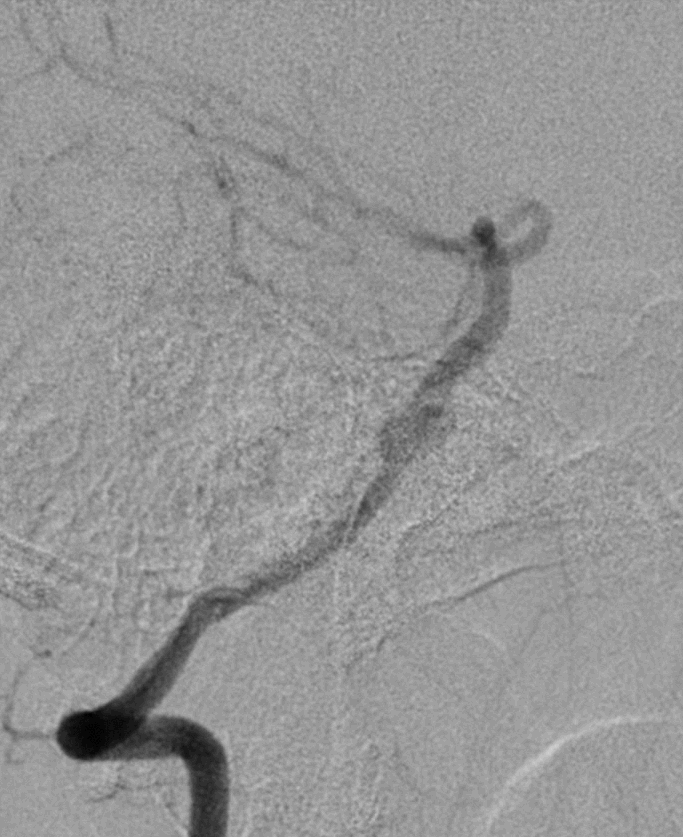

术后3月余复查:

动脉瘤愈合,支架内血流通畅。

传统弹簧圈填塞治疗后循环不规则动脉瘤,并发症发生率高且治愈率低,本病例动脉瘤位于基底动脉近端,瘤颈较宽,使用Tubridge血流导向密网支架进行基底动脉不规则动脉瘤治疗,减少了围手术期并发症,改善患者的预后效果。